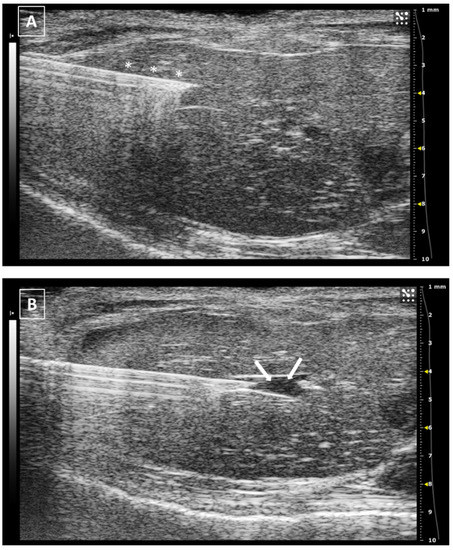

The needle can be seen inside the left ventricle as a hyperechoic linear structure with reverberation artifacts in an anechoic background. During the injection, we will be able to see some small hyperechoic dots coming from the needle. These are microbubbles created during the needle filling. These dots will confirm the correct injection in the anechoic ventricular cavity. Once the injection is completed, the needle can be removed. An example of an intracardiac injection can be seen in Figure 3.

The duration of this process depends on the expertise of the user. An experienced ultrasonographer can do the injection in less than a minute. The major risk of this procedure is the incorrect injection in the right ventricle, the lung, or the mediastinum. We will not see the hyperechoic bubbles arising inside the left ventricle. Other less frequent errors can be damaging the aorta the cava vein or any of the cardiac atriums. In these cases, we will see an acute intrathoracic hemorrhage.

Figure 3. Intracardiac injection. (A) Preinjection image. Needle is marked with white asterisks and left ventricle area is surrounded by a dashed line. Lung artifact is labeled with white arrows. (B) Injection moment. Multiple white dots (marked with white arrows) inside the left ventricle correspond to microbubbles injected with the suspension. Images obtained with 40 MHz frequency.